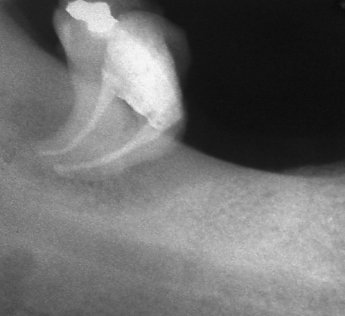

Добре пролекувани зъби

Ендодонтия